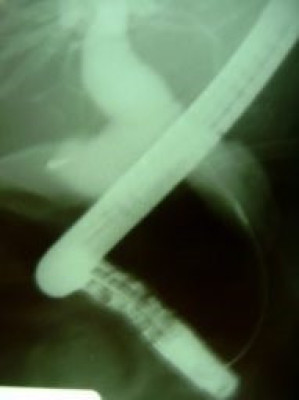

Quiste de coledoco tipo II

Envíado por Dr. Carlos Miguel Zavaleta Consuegra